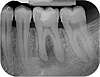

Radio des dents

N°3

radiographie dents